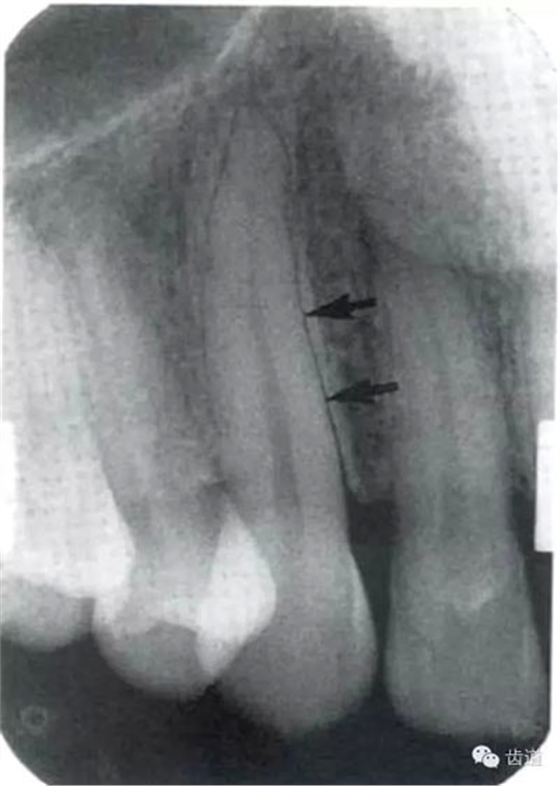

2)營(yíng)養(yǎng)管:

常見(jiàn)于下頜前牙區(qū),在牙根之間的牙槽骨內(nèi)并與牙長(zhǎng)軸平行的密度低的條狀影像。此為小血管進(jìn)入牙槽突的影像。